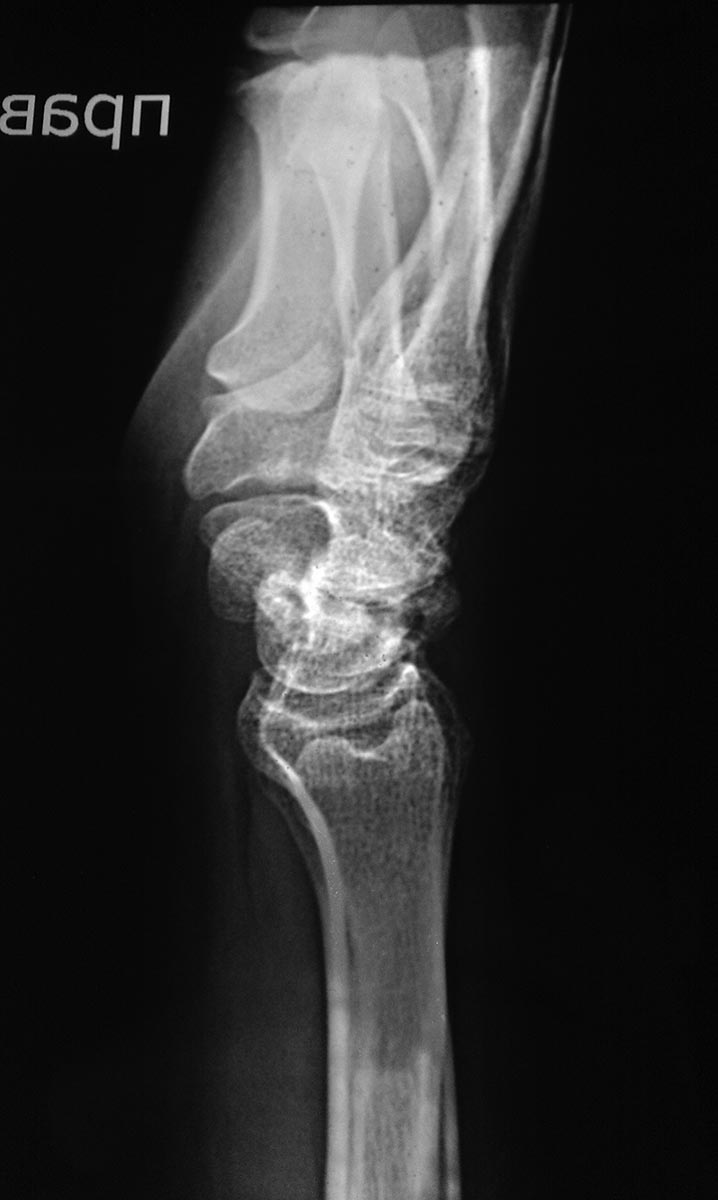

[Ortho] Перелом (ложный сустав?) ладьедидной кости правой кисти

Снимок от 18.03.16 после закрытой репозиции на аппарате Илизарова.